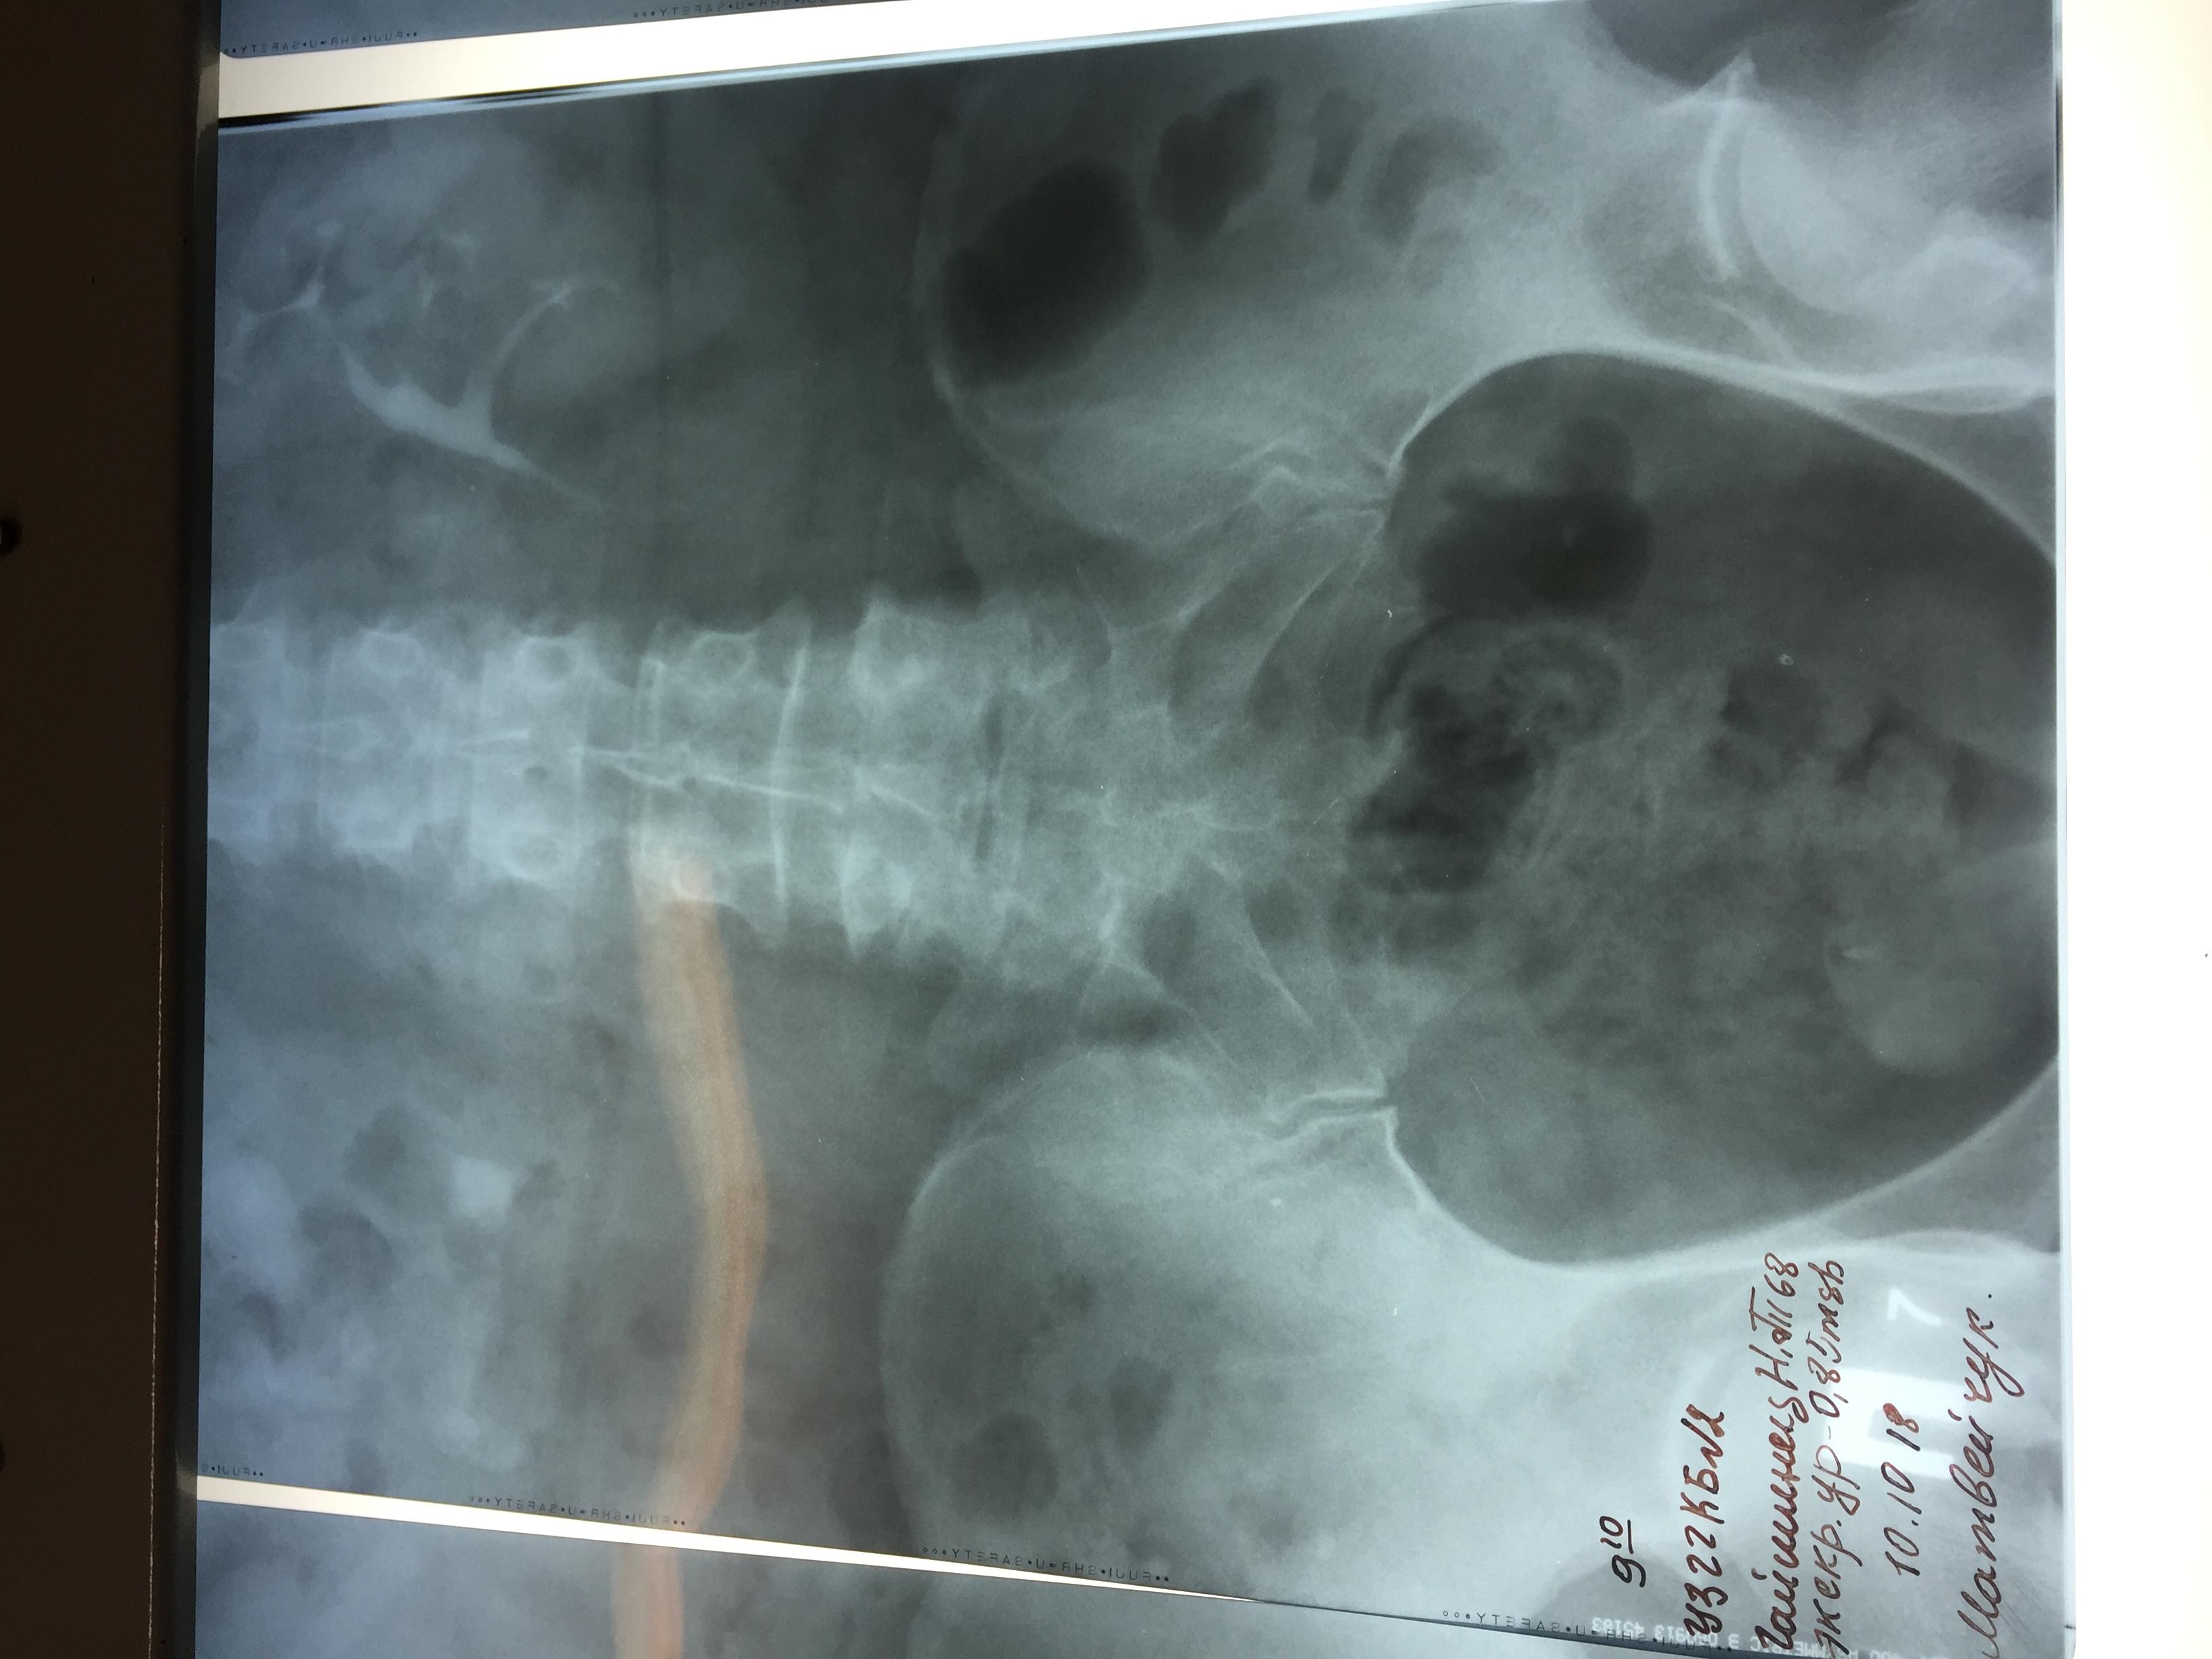

Камень в почках размер 25 мм

Беспокоила тяжесть в почке и периодические боли, часто выходили мелкие камни, после очередного приступа обратилась к врачу и попала в Больницу, сделали снимки ( фото прилагается) обнаружен крупный камень размером 25 мм и несколько мелких . Что делать? Не знаю? Дайте пожалуйста рекомендации!!! Удалять камень? Каким способом операция либо новыми технологиями это возможно?